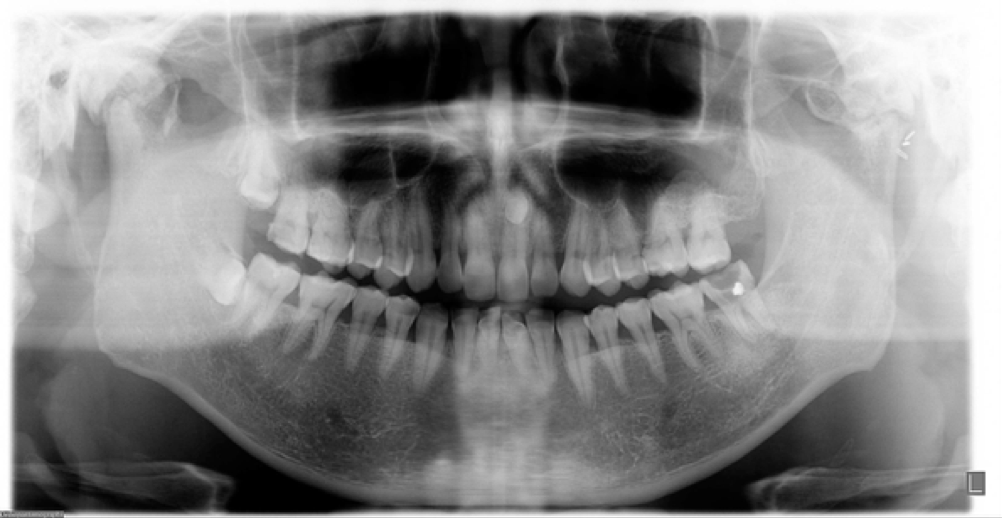

인공턱관절 치환술은 외과적으로도 안정적인 수술 결과를 보여주고 있다1-4). 턱관절의 수술은 여러가지 면에서 난이도를 가지고 있는 수술이다. 인공 턱관절은 CT 데이터를 이용하여 환자의 결손부에 적절하게 디자인하는 customized device와 미리 정해진 크기의 관절장치를 이용하는 stock device 로 나뉘어진다. 환자의 해부학적인 구조에 따라 맞춤형 장치를 쓰는 것이 이상적이기는 하지만 환자의 해부학적 인 차이가 크지 않으며, 반드시 미리 계획을 하지 않아도 수술 시 필요에 따라 선택할 수 있고, 비용적인 측면에서 장점을 가진다고 할 수 있다는 측면에서 stock device는 장점을 가진다고 할 수 있다5). 우리나라에서는 현재 stock device만 허가를 받아 사용할 수 있는 상태이다. 인공턱관절의 수술은 관절와 부분의 삽입과 과두부분의 삽입을 위한 외과적 접근으로 이루어진다. 관절부의 접근을 위해 전이개부절개가 주로 이루어지며, 과두부의 삽입을 위해서는 하악 후방 절개가 사용된다. 외과적 술식에 동반된 합병증으로는 안면신경의 손상과 수술 후 감염이 가장 주된 합병증이다. 본 종설에서는 stock device 를 이용한 수술과정에 대해 설명할 예정이다.

Fig. 1 양측 턱관절 강직증으로 개구량 15 mm의 개구제한